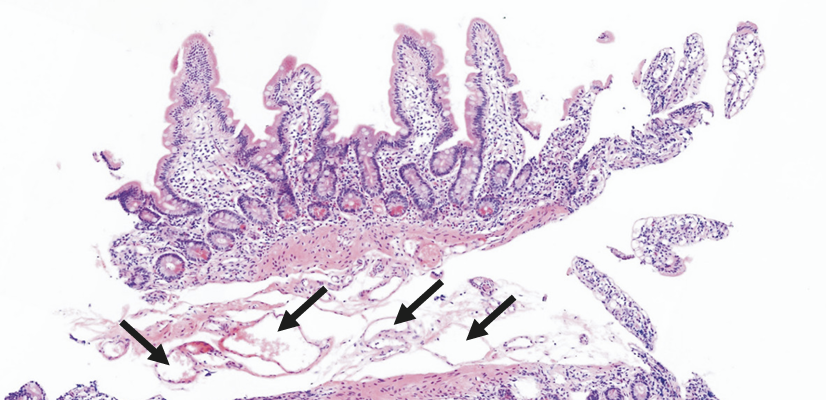

Intestinal lymphangiectasia is a rare condition where tiny vessels in the intestine, called lymphatic vessels, become enlarged and leak a fluid called lymph into the gut. This can cause the body to lose important proteins, leading to low protein levels in the blood and swelling in the legs, feet, or face.

Intestinal lymphangiectasia is classified

into primary or secondary types. Primary intestinal lymphangiectasia, also called idiopathic

lymphangiectasia, occurs congenitally in the absence of causative factors. Secondary

intestinal lymphangiectasia is induced by risk factors including heart surgery, chemotherapy,

infection, or toxic materials known to trigger lymphatic changes